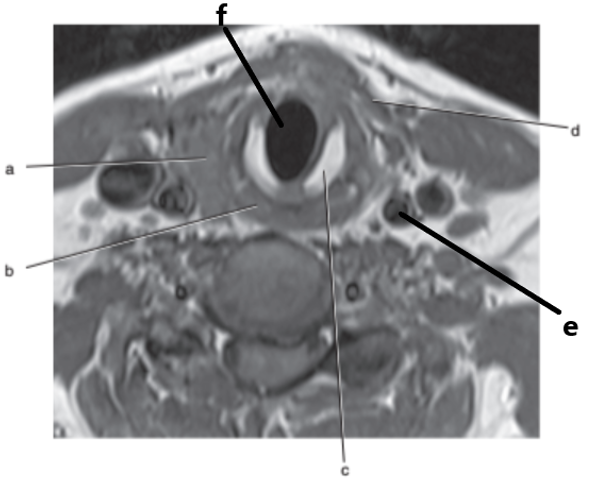

What is letter c ?

Cricoid cartilage

Trachea

What is letter a ?

Vertebral artery

Aortic arch

What is letter b ?

Thyroid gland

What is letter g ?

Vocal cords

What is letter d ?

Internal carotid artery

What is letter f ?

Spinal cord

Internal jugular vein

Common carotid artery

Esophagus

Basilar artery

Carotid sinus/bifurcation